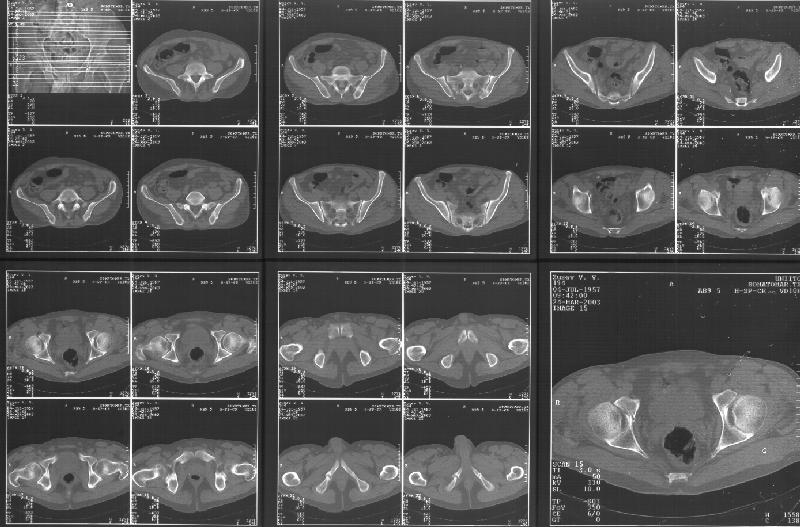

Прилагаю свежую КТ таза.

Буду признателен за комментарии и предложения по тактике.

Картинки см. ниже, левая - с экранным разрешением, вторая - полноразмерная, ~900 кб.

КТ в экранном разрешении

Полноразмрная картинка, около 900 кб

Based on the CT images you provided, he appears to have a nonunion of the the right ischium, which would explain his symptoms. General principles of treatment of hypertrophic (which this appears to be) nonunions suggest rigid fixation, but I'm not sure what the best approach would be. Could get a lag screw across the fracture through a Kocher-Langenbeck approach or plate osteosynthesis through direct ischial approach, but perhaps Chip, Adam or someone with more pelvic fracture experience could enlighten us all.

I think the CT cuts in question are on the right of the bottom row i.e.

http://www.hwbf.org/hwb/conf/alex47/image3a.jpg

Thanks for the link to the plain films and CT images.

I think this is just a pelvic ring disruption that has gone on to a non-union. The arrow is pointing to the inferior ramus non-union, and

the sup ramus is a high "root" fracture, right near the pecten. The sup ramus fracture enters the tab - you could call it an acetabular

fracture - but down here in Dallas we treat these acutely as stable pelvic ring injuries. The fracture in the anterior portion of the

acetabulum is so low it doesn't seem to cause much trouble.

His R sacroiliac joint is opened anteriorly a little bit - the "unreduced posterior lesion" Alex mentioned in his first post. My earlier post about plating, bone grafting, etc., is all wrong.

What you have is a pelvic fracture that hasn't healed after 4 months or so, with a minimal deformity.

I think what I would offer the guy is a percutaneous iliosacral screw to stabilize and improve the SI joint alignment, coupled with a perc anterior column screw to stabilize the high ramus fx. These screws aren't easy to place, and have a host of potential problems and complications. But, I think they would work.

Как Вы сами видели на томограммах, грубых деструктивных явлений крестцово-подвздошного сочленения не определяется( маркировка правая -левая сторона не видна), определяется сравнительно незначительное расширение суставной щели с одной стороны и не более того.

Виноват, первый раз не обратил внимания на возможность полноформатного просмотра томограмм. В этой связи -дополнения к своему первому комментарию: сросшийся перелом вертлужной впадины справа, L5-S1 спондилоартроз, расширение суставной щели крестцово-подвдзошного сочленения справа может компрометировать его стабильность и вызывать локальные боли, но вряд ли это может давать двусторонние проявления в нижних конечностях. Все-таки миелограмма или ЯМР желательно иметь, чтобы определиться в тактике.